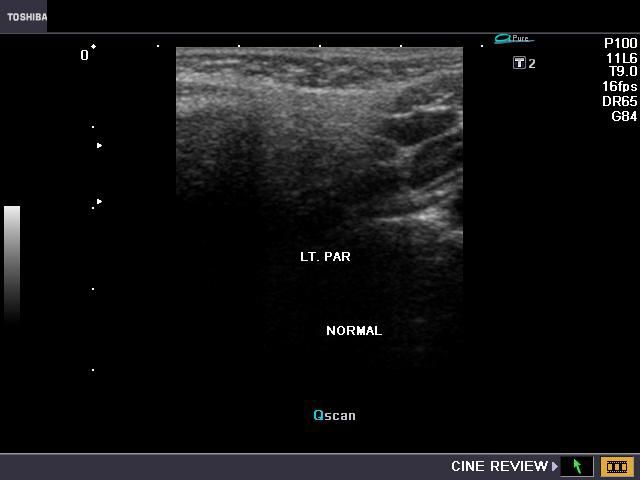

B) Parotid gland

The normal parotids.

The parotid gland is much larger than the submandibular salivary gland. Its transverse diameter is considerably smaller than the coronal dimensions. The parotidshows almost the same texture and echogenicity as the submandibular gland.